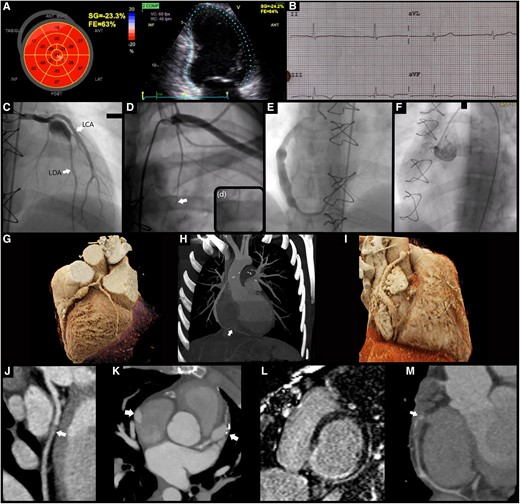

Twice the spice: a unique association of hypertrophic cardiomyopathy and pericardial agenesis by @EHJCVIEiC Mónica Dias et al. ☑️ https://t.co/07d4qkUXbL A rare combo: 47-yo man with hypertrophic cardiomyopathy (#HCM) and partial congenital pericardial agenesis 🫀